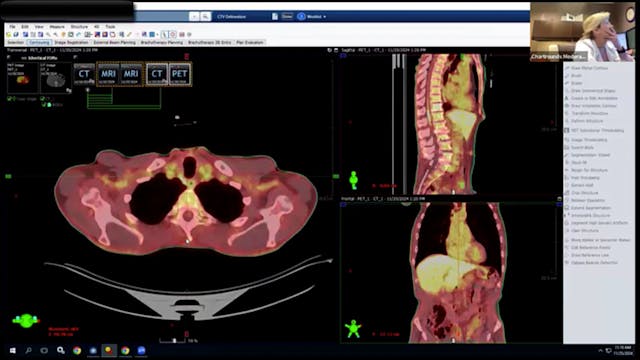

Head and neck cancerOropharyngeal cancer

HPV-associated squamous cell carcinoma

Tumor staging (T3 N2, AJCC)

Carcinoma with extranodal extension

PET/CT imaging

Radiation oncology case discussion